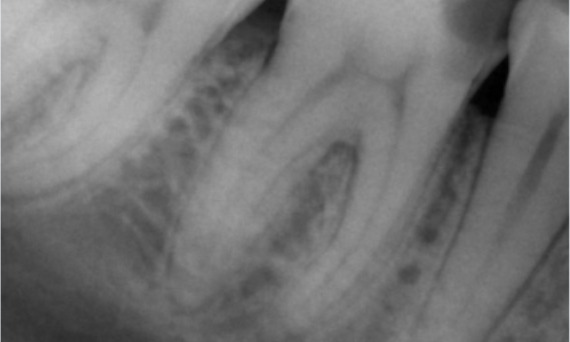

Before: Upon examination, there was a caries lesion related to the lower right first molar. Radiographic examination revealed proximity of the lesion to the pulp horn and combining it with the chief complaint, a final diagnosis of chronic irreversible pulpitis was concluded.

After: Access cavity was done as conservative as possible. TruNatomy was the system of choice due to the young patient’s age. We needed to preserve dentine as much as possible to increase the tooth ability to overcome occlusal load and increase the longevity of the final restoration.